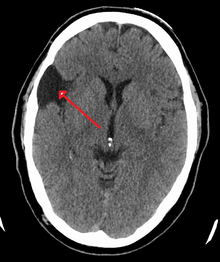

Arachnoid cyst as seen on a CT image of the brain

Axial CT showing a typical arachnoid cyst left temporal

Diagnosis is principally by MRI. Frequently, arachnoid cysts are incidental findings on MRI scans performed for other clinical reasons. In practice, diagnosis of symptomatic arachnoid cysts requires symptoms to be present, and many with the disorder never develop symptoms.